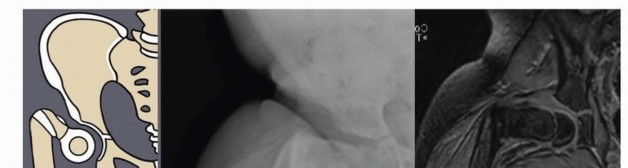

Illustration 3 for Treatment for Congenital Femoral Deficiency: What You Need to Know Illustration 4 for Treatment for Congenital Femoral Deficiency: What You Need to Know Illustration 5 for Treatment for Congenital Femoral Deficiency: What You Need to Know Illustration 6 for Treatment for Congenital Femoral Deficiency: What You Need to Know FIG 2 • A. Paley type 1b CFD (subtrochanteric type) shown by illustration, radiograph, and MRI. Note the nonossified subtrochanteric cartilage B. Paley type 1b CFD (neck type) shown by illustration, radiograph, and MRI. Note the nonossified neck. *

Other imaging studies that are useful include magnetic resonance imaging (MRI) and arthrography of the hips. All Paley types 1b and 2 should have an MRI after age 18 months to confirm whether there is a cartilaginous connection between the femoral head and shaft (

FIG 4 *).

in the proximal femur, and the CFD is classified as type 1b. The arthrogram is also useful to differentiate between Paley types 2a and 2b. Both 2a and 2b might have a femoral head present; the difference is whether the femoral head is fused to the acetabulum or not. If dye can be injected into a joint space, the hip can usually be classified as type 2a. In some cases of type 2a, the dye can be seen to outline a cleft through the femoral neck. Illustration 8 for Treatment for Congenital Femoral Deficiency: What You Need to Know Illustration 9 for Treatment for Congenital Femoral Deficiency: What You Need to Know FIG 4 • MRIs of Paley type 2 CFD. The femoral head is clearly seen (A), and in a separate cut, one sees the proximal femur in a different plane (B). *